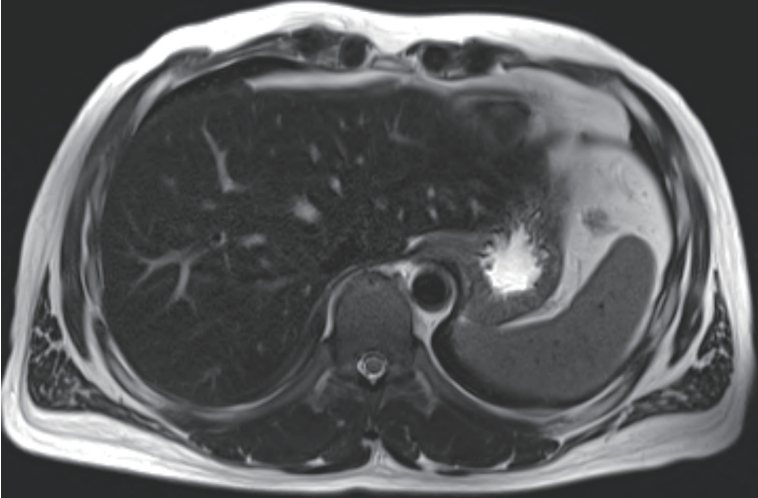

Given the improving liver function and elevated ferritin as a possible acute phase reactant, we initially considered that the patient was in the recovery phase of acute hepatitis A. Supportive treatment was continued, and serial laboratory follow-up was performed. Although total bilirubin levels gradually decreased during follow-up, AST and ALT levels rose again to 231 U/L and 409 U/L, respectively. Serum ferritin remained elevated (1,305 ng/mL), and transferrin saturation was also persistently high (53.4%). To evaluate hepatic iron deposition, liver MRI was performed. On T2-weighted imaging, the hepatic parenchyma showed relatively low signal intensity compared to the spleen, suggestive of iron accumulation (

Fig. 1).

Figure 1.Liver Magnetic Resonance Imaging at the time of liver biopsy. On T2-weighted imaging, the hepatic parenchyma shows relatively low signal intensity compared to the spleen.